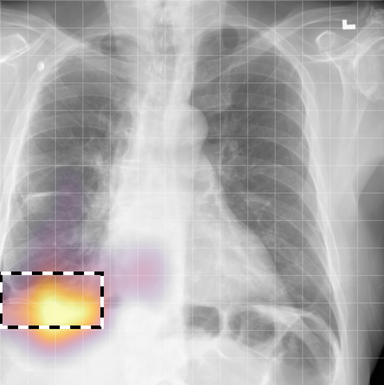

for , where denotes 2D sinusoidal positional encodings [12] and is its temporal counterpart, which is learnt (Fig. 2) [4]. The layer-normalised () [6] output of the final transformer encoder block is an ‘aggregated’ representation of patch-level progression information anchored on the current image. Figure 3 shows attention roll-out [1] applied to after pre-training, showing how the prior image contributes to the fused representation. Figure A.5 further highlights the robustness to variations in pose underlining that registration is not necessary for this encoder.

In Figure A.3, we show examples of self-attention rollout [1] maps for pleural effusion and consolidation, including radiologist-annotated bounding boxes surrounding the corresponding pathology in each prior and current image.

To model the attention flow through the transformer encoder block, we first average each attention weight matrix across all heads, subsequently we multiply the matrices between every two layers. For every block we add the identity matrix in order to model the residual connections. Last, we only keep the top 10 of attention weights per block to reduce noise in the final rollout map. In contrast to [21], we do not visualize the rollout map with respect to a [CLS] token. Instead, we choose a reference image patch from the center of the radiologist-annotated bounding boxes, marked with in Figure A.3.

We find that the rollout maps in Figure A.3 are in good agreement with radiologist-annotated bounding boxes, i.e., the reference patch attends to other patches within the bounding boxes in the prior and current image. In addition, we find that BioViL-T is robust to pose variations, e.g., in Figure A.3 (a) we show that despite the vertical shift between prior and current image, the reference patch attends to the correct image patches in the prior image.

To further assess the robustness of BioViL-T against pose variations between prior and current images, we performed multiple rotations to the prior image within a pair and computed rollout maps from the same reference patch in the current image. Figure A.5 shows that BioViL-T consistently attends to the corresponding anatomical region independently of the spatial transformation applied, demonstrating that registration is not needed.